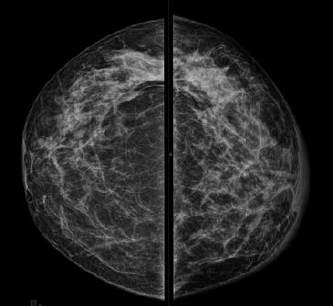

Uma paciente de 46 anos realizou esta mamografia.

Assinale a alternativa que contém a descrição e a classificação BIRADS correspondente.

A

Mamas densas sem evidência de nódulos visíveis ou linfonodomegalia axilar. BIRADS 1.

B

Assimetria focal e linfonodos intramamários no QSE da mama direita. BIRADS 3.

C

Infiltração cutânea e aumento difuso da densidade da mama esquerda. BIRADS 5.

D

Ectasia ductal retroareolar e linfonodo intramário no QSE da mama esquerda. BIRADS 2.

E

Assimetria focal no QSE e espessamento cutâneo retroareolar da mama direita. BIRADS 5.